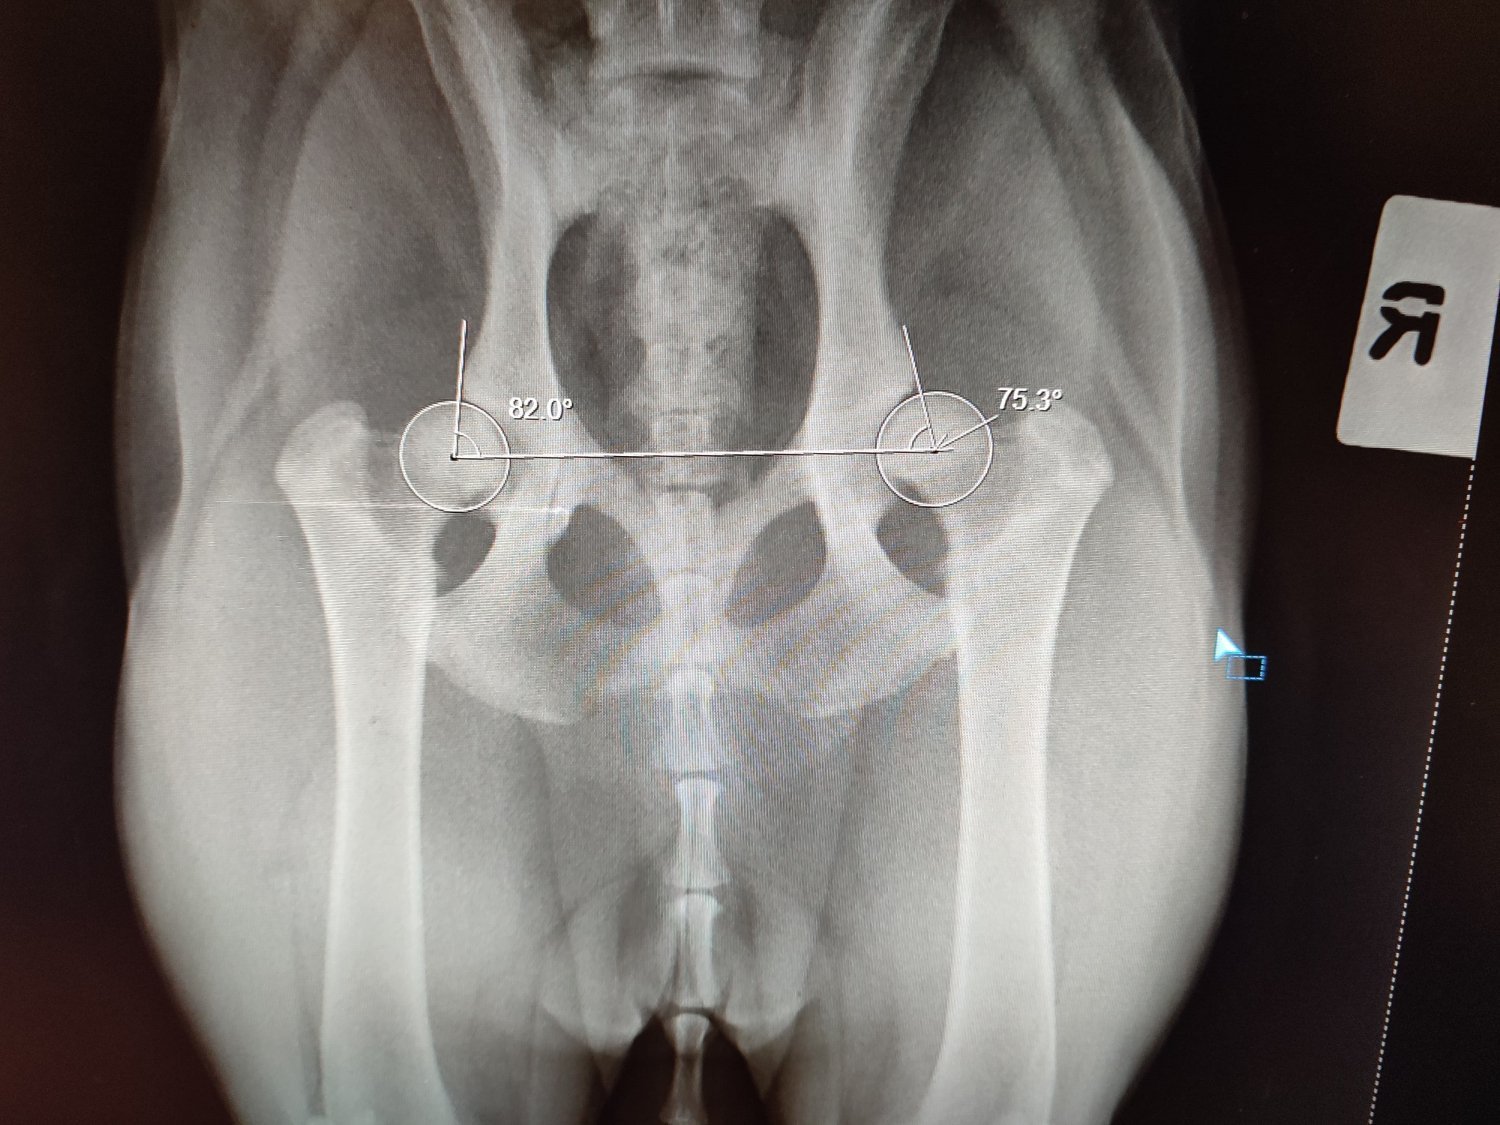

Zrzutki ciąg dalszy, na operację drugiego stawu. Ten staw jest lepszym stawem, ale i on zdiagnozowany jest jako zaawansowana dysplazja. Na tą chwilę Lila ma się dobrze, czasami pomarudzi z nudów bo musimy ją trzymać odizolowaną, żeby ograniczyć jej ruch do minimum, ale humor jej dopisuje kiedy się powymiziamy. Na szczęście pracuje z domu i biuro przeniosłem do tego samego pokoju. 2 operacja będzie taka sama jak pierwsza, czyli darthoplastyka, przeszczep kości. Na jej starym stawie już widać poprawę, nie "słychać" kości jak chodzi, rana po operacji dobrze się zagaja. Niestety ten miesiąc jest miesiącem bardzo chudym, bo przez operację wypłukaliśmy się do zera, dlatego nie zamykam zrzutki i mam nadzieję na drobne chociaż wsparcie. Bardzo wam wszystkim dziękuję za dotychczasowe wpłaty, bez nich nie bylibyśmy w stanie nawet zacząć tej podróży ku zdrowiu naszego kochanego psiaczka

Cześć, zrobiłem zrzutkę ponieważ sam sobie z tym nie poradzę. Mam małego-dużego szczeniaczka, kochaną Lilę która ma 8 miesięcy i 30kg. Strasznie szybko rosła przez ostatnie miesiące co spowodowało że rozwinęła się u niej zaawansowana dysplazja biodrowa. To było coś czego się spodziewałem, w końcu to mieszanka labradora z owczarkiem niemieckim, natomiast nigdy nie wyobrażałem sobie, że będzie tak źle, że skończy się to operacją. Główki kości udowej nie wchodzą w panewkę miednicy, co powoduje ścieranie się chrząstki, ból i kicanie podczas biegania. Lila to bardzo kochany piesek, zabrałem ją jako szczeniaczka od pewnej sąsiedzkiej wpadki. Chciałem dać jej dom, schronienie i miłość, teraz chciałbym móc również zadbać o jej zdrowie. Czekają ją 2 operacje, jedna to DPO, podwójne cięcie miednicy, jej miednica zostanie "złamana" w pół, żeby nałożyć tą miednicę, aby główka wchodziła w panewkę. To na pewno pomoże na jej lepszy, lewy staw. To właśnie na tą operację zbieram. Kolejna, która kosztuje kolejne 4000 do dartoplastyka. Tą zapłacę samemu, jeżeli uda mi się dostać kredyt. Polega ona na przeszczepie kości, aby prawy staw nie wypadał, a miał więcej miejsca do podparcia. Z tego co rozumiem, dopiero po tych dwóch operacjach jej gorszy staw w końcu będzie się do czegoś nadawał. Do biegania wśród psiaków, do ganiania za patykami, do radosnego i bezbolesnego dzieciństwa. Za każdą, nawet najmniejszą wpłatę będę bardzo wdzięczny,